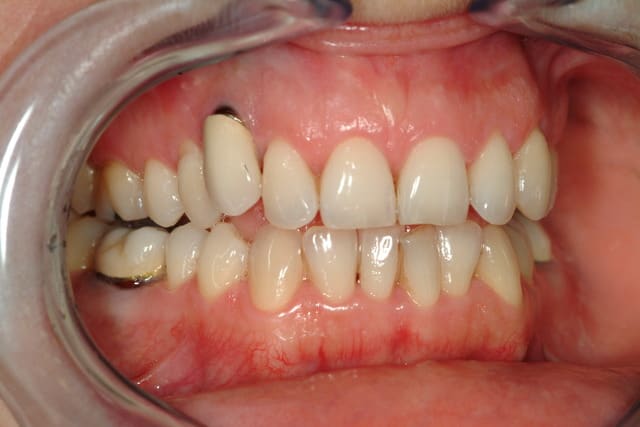

Il me semble que c’est le liserai du pilier qui est visible, que l’ajustage la couronne soit perfectible et que l’on aperçoive légèrement l’implant.

L’espace entre 12 et 14 est trop faible pour aligner la 13 qui est trop courte sur bord incisif.

Avant de faire de gros travaux j’opterai pour ta solution avec un pilier sur mesure en zircone voir teinté en rose.

Pour la 13, c'est l'implant ou le pillier qui est visible ?

Type d'implant ?

Si c'est un hex externe, tu peux tailler un peu le buccal...

pillier métal avec céramique rose et couronne Zircone...